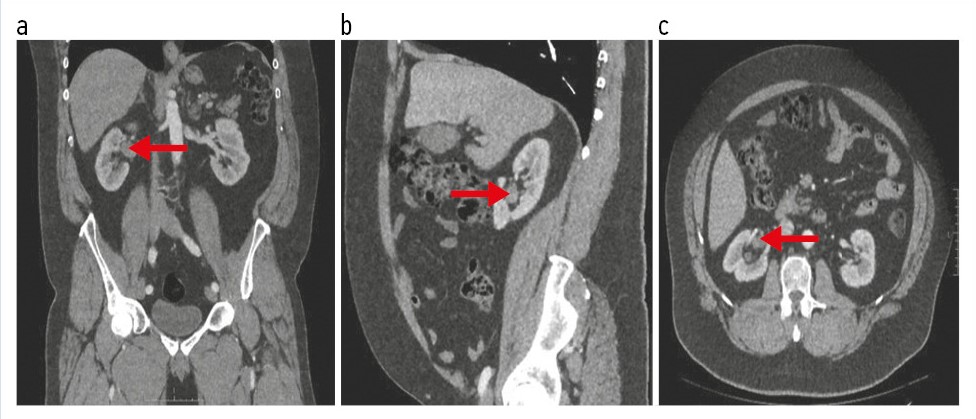

С целью дифференциальной диагностики выявленного образования в почечном синусе и более точной оценки распространенности выполнена МРТ почек и надпочечников с внутривенным контрастированием. В синусе правой почки определяется овоидное образование неоднородной структуры преимущественно пониженного сигнала в режимах Т2 и Т1, неоднородно накапливающее контрастный препарат, с рестрикцией диффузии, размерами 30×17×22 мм, тесно прилежащее к ветвям почечной артерии и вены. Периренальная клетчатка – без особенностей (рис. 2).

Рис. 2. Пациент Г., 56 лет. МРТ органов брюшной полости и забрюшинного пространства с контрастированием. На корональной (a) и аксиальной (b) постконтрастных магнитно-резонансных томограммах в синусе правой почки определяется овоидное образование неоднородной структуры пониженного сигнала в режимах Т2 и Т1.